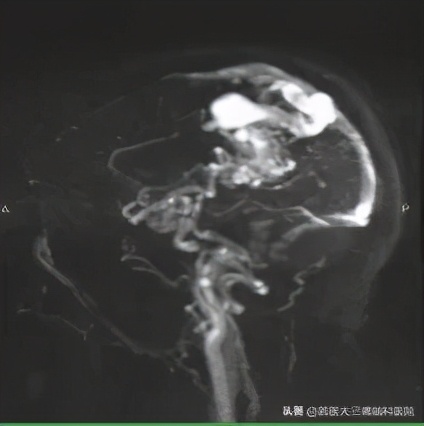

妊娠27周孕妇突发脑出血多学科协作紧急救治 首医大三博脑科医院 Mdeditor